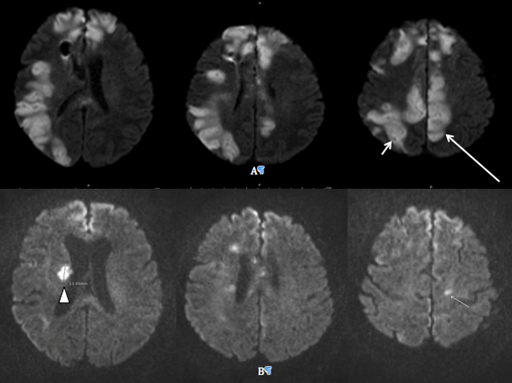

On postoperative day 4, follow-up MRI continued to show no evidence of hemorrhage but revealed new ischemic areas in the posterior cortex paramidline apex and the right post central gyrus (Figure 2). 2D Echocardiogram was performed to rule out a cardiogenic etiology and revealed moderate to severe asymmetric septal hypertrophy, mild left ventricular diastolic dysfunction, and hyperdynamic left ventricular systolic function. CTA revealed scattered, multifocal stenosis of the bilateral M1 segments and of the left A1 segment confirming the diagnosis of vasospasm. Treatment with nimodipine and triple H therapy was immediately initiated. Due to persistent respiratory failure and prolonged ICU stay, the patient was tracheostomized.

Figure 2 Postoperative day 4 MRI DWI axial views (A) show ischemic areas in the posterior cortex paramidline apex (long arrow) and the in the right post central gyrus indicating an evolving stroke (short arrow). (B) Postoperative day 19 MRI DWI axial view demonstrating new infarct in area of right head of the caudate (arrowhead).

On postoperative day 19 a new area of infarct was noted on routine CT and MRI in the area of the right head of the caudate (Figure 2). No changes in the patient neurological exam were noted at this time. CTA again revealed no changes in the aforementioned aneurysm from baseline or any signs of occlusion and continued to reveal no acute hemorrhage.